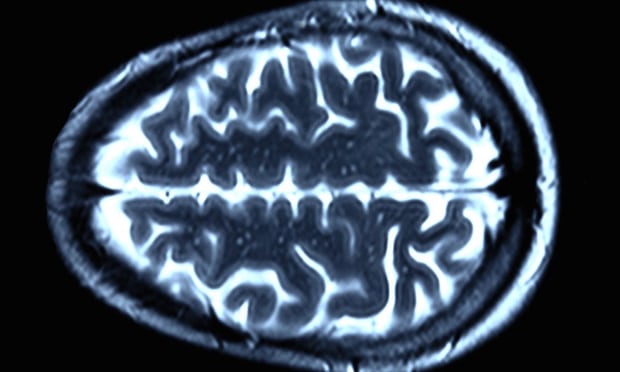

MRI scan of a healthy brain. Image taken from The Guardian.

A new drug has been shown to have positive effects on slowing down or even suppressing the effects of Huntington’s Disease, a genetic illness that causes nerve cells to break down and damage the brain. The University College London Huntington’s Disease Center led this groundbreaking discovery, exciting the entire scientific community. The new drug used has the potential to be cures for other fatal brain diseases in the future.